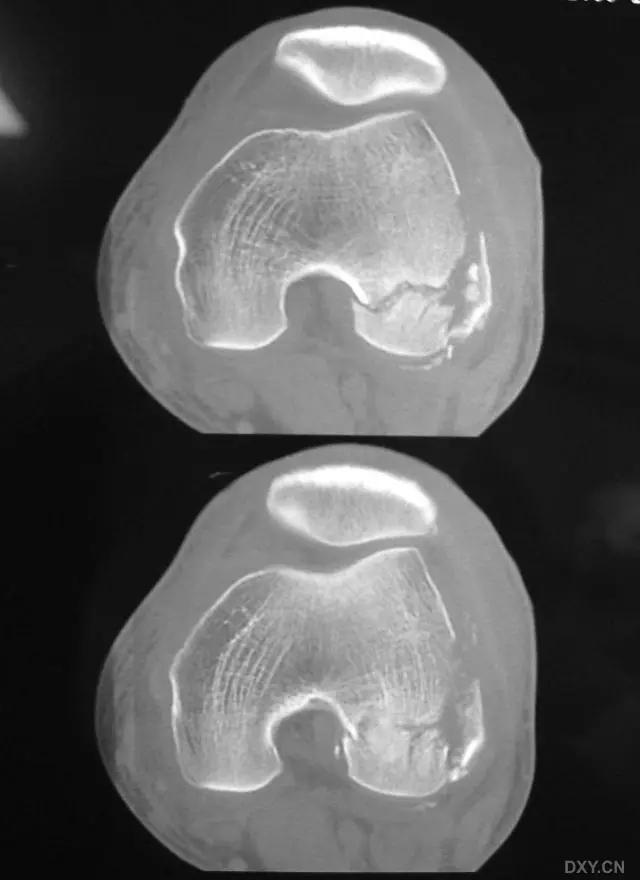

5. Hoffa 骨折

指股骨远端冠状面的骨折。

病例 1:一般股骨髁间、髁上粉碎骨折中含 Hoffa 骨折的不少见,但单纯后髁骨折则很少见。

水平位 CT